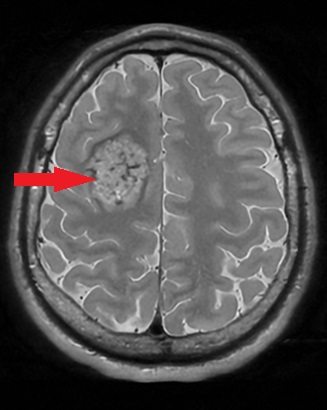

- Zmiany zapalne (np. stwardnienie rozsiane, ostre rozsiane zapalenie mózgu i rdzenia)